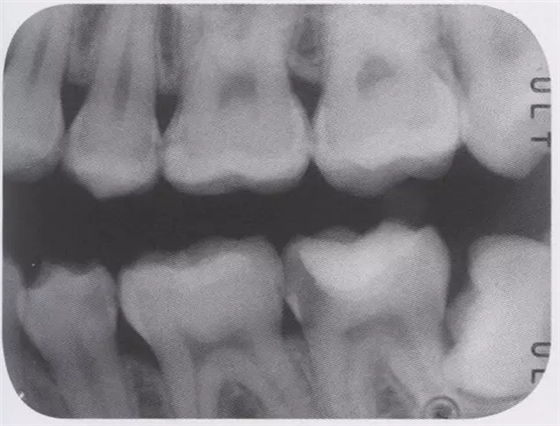

圖3 全瓷嵌體的修復(fù)(右56)。鄰接面產(chǎn)生齲齒的情況(上段,中段左),去除齲齒,并佩戴嵌體(下端)。